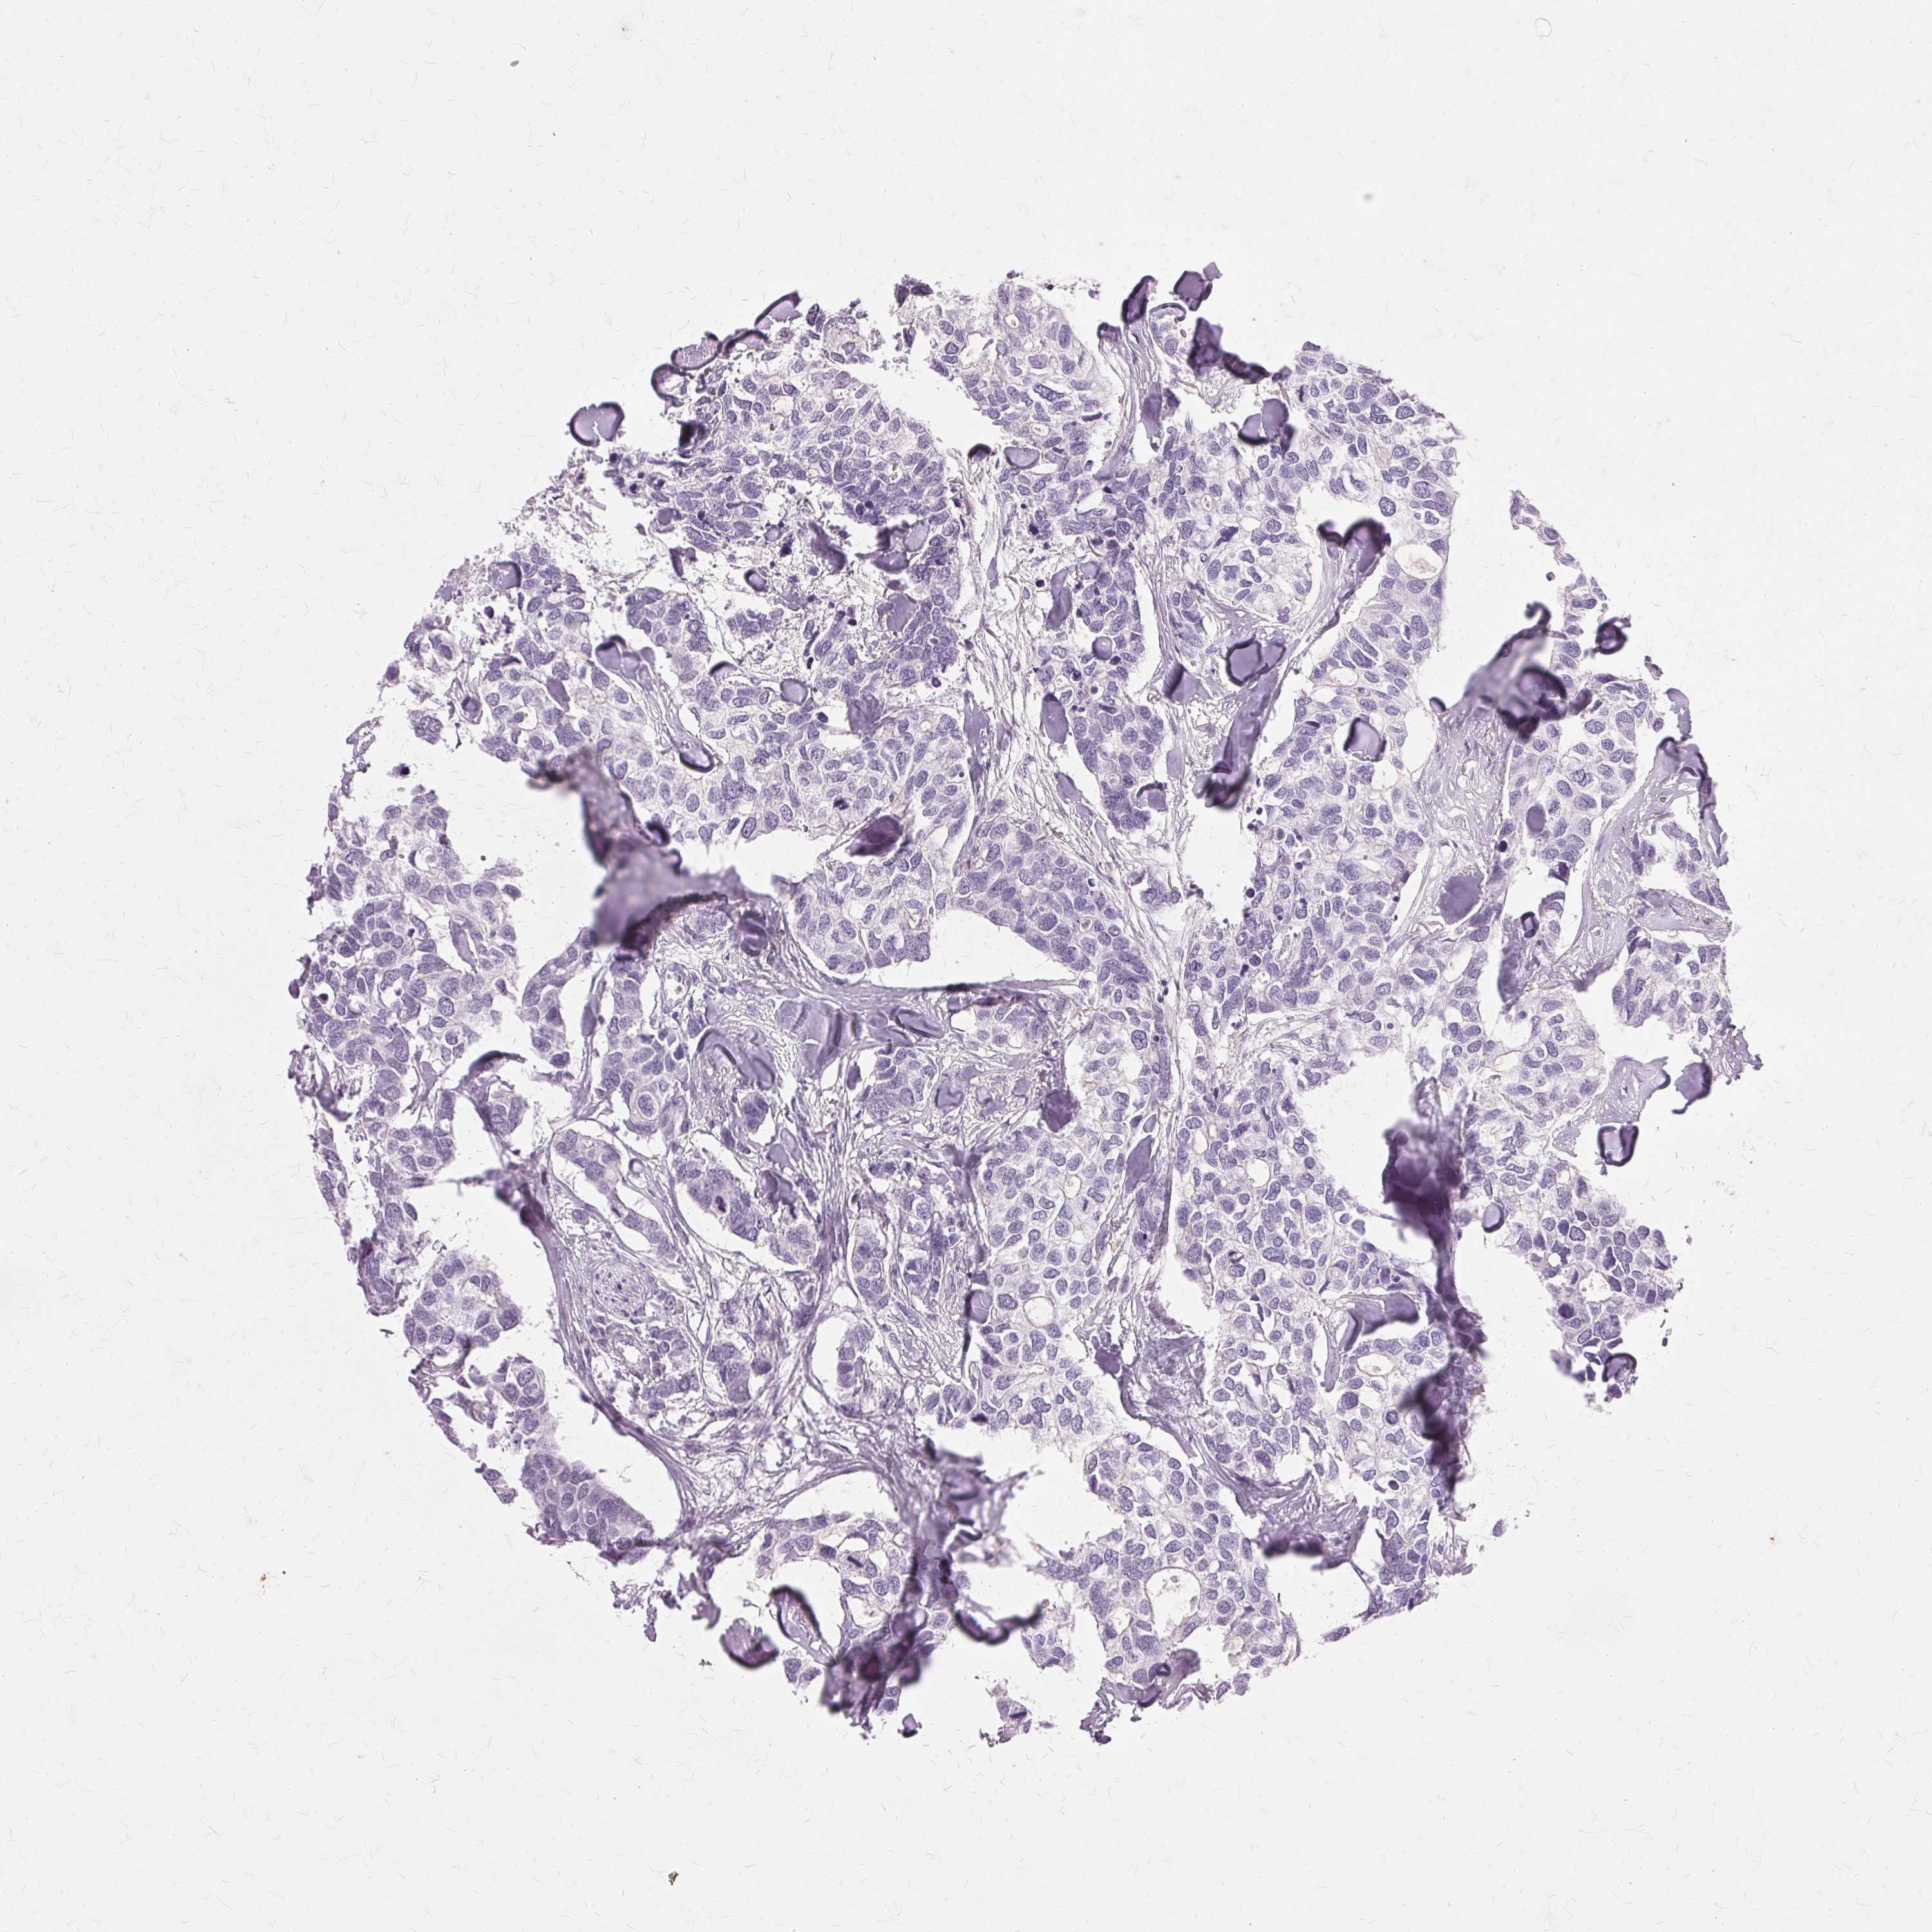

Breast cancer

Human cancer

Breast invasive carcinoma